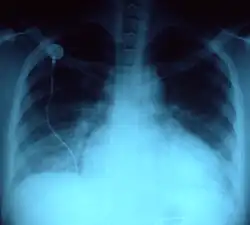

- No morfotipo brevilíneo, indivíduos com o tórax largo, uma distância púbis-pé menor que a distância púbis-vértice, muitas vezes com excesso de peso e um diafragma elevado, o coração está numa posição mais horizontal. O impulso apical é desviado para acima do 4º espaço intercostal e para fora da linha médio-clavicular, na linha axilar anterior e mesmo por vezes na linha axilar média. Numa radiografia do tórax o coração aparece "deitado" sobre o diafragma dando um falso aspecto de dilatação cardíaca porque o índice cardiotorácico (sinal radiológico: razão entre o diâmetro do coração e o diâmetro torácico) está aumentado.[2]